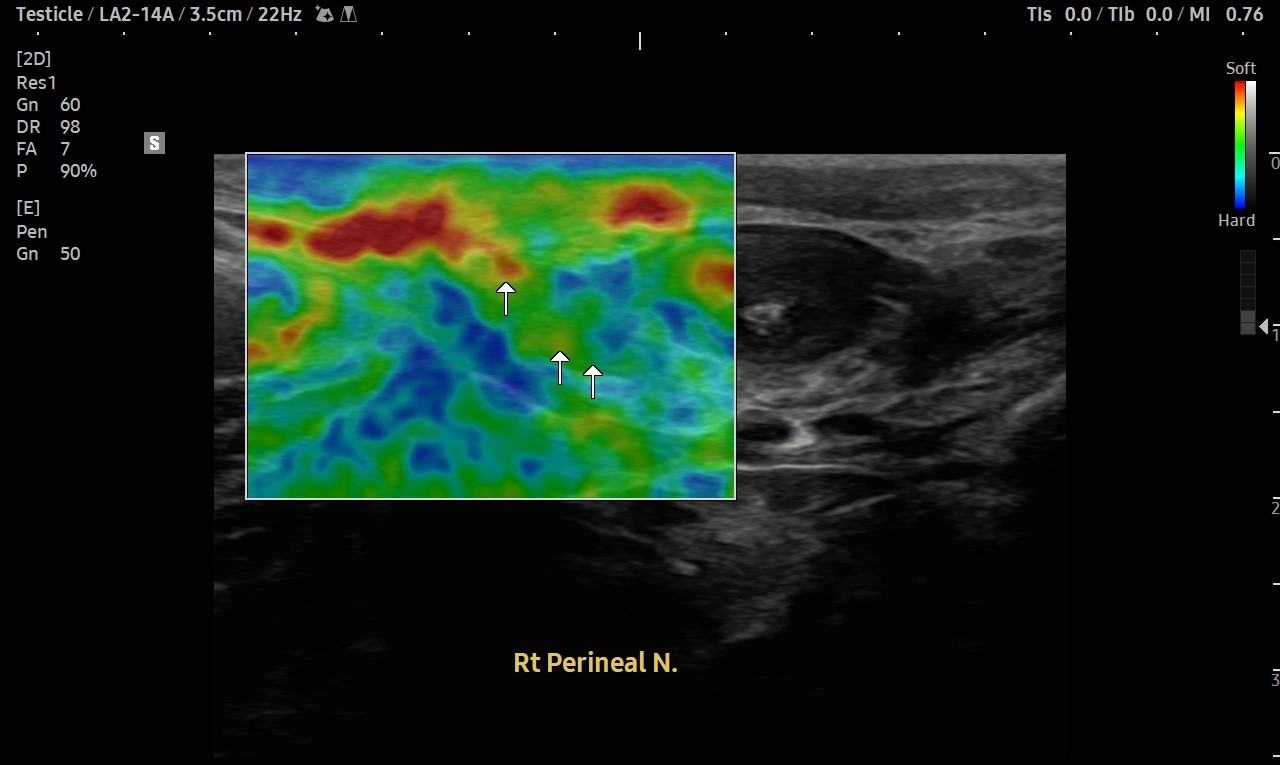

통증 부위를 살펴볼까요?

회음부의 통증과 치골부위 통증이 심했습니다.